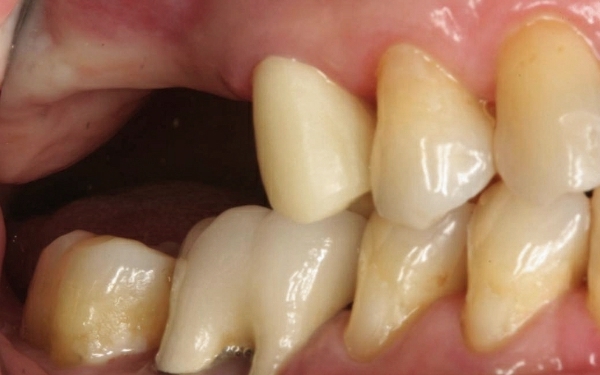

上排缺牙區

最後裝置假牙

完成照片